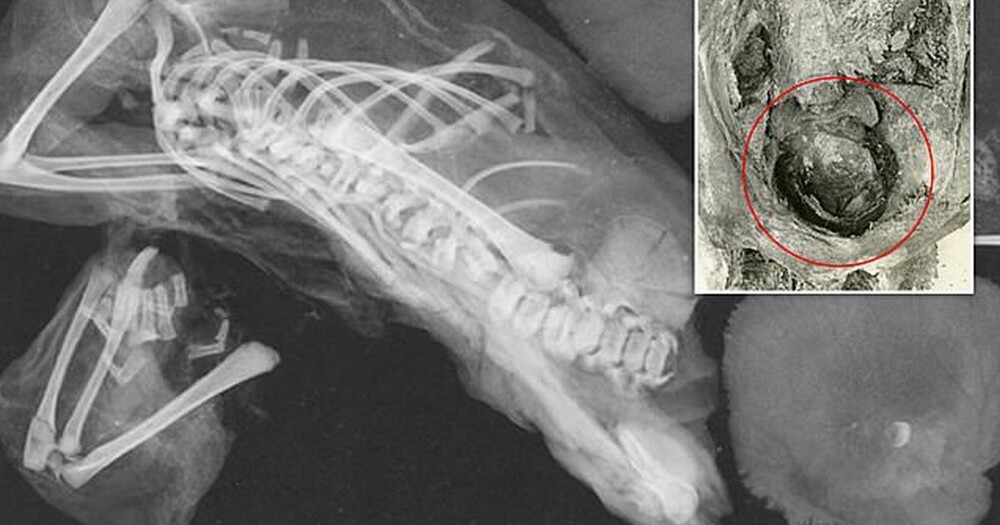

Researchers at George Washington University performed a CT scan of the body, finding a baby's head stuck in the birth canal and another fetus somehow displaced into the chest cavity.

Apparently, the older twin died from traumatic decapitation of the fetus, and the younger twin separated from the uterus and moved to the ribs.

In their work, the researchers used records from 1908, from which it follows that scientists who studied the mummy earlier turned the body around, removed the arms, processed the thigh bones and made an incision on the stomach. The entries also mention a headless baby between her legs, covered in a sheet and layers of salt.

A CT scan revealed a baby in the upper left side of the mummy's chest cavity, showing long bones, ribs, neural arches, a skull and five arm bones. The available records only spoke of the first twin and made no mention of the second fetus. It was only now that they were able to discover it. Scientists were able to determine the age of death of children - 36-40 prenatal weeks. This proves that they were twins.

Old records did not indicate a cause of death, but using photographs and CT scans, researchers concluded that the cause of death was fetal head impingement during a breech birth.

“The detection of the fetal head at the pelvic inlet strongly suggests that labor is delayed,” the study says. “Probably the reason for the delay in labor was the breech presentation of the fetus.”

How the second fetus migrated into the chest cavity is still unclear. It may have been mummified along with other internal organs. During the mummification process, the diaphragm and connective tissue in this area may have resorbed, allowing the unborn baby to move into the chest cavity.